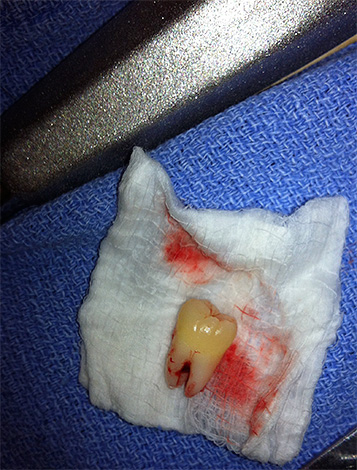

- Após algumas operações, por exemplo, imediatamente após a extração dentária (na linguagem dos cirurgiões-dentistas, as extrações dentárias são simples e complexas e, às vezes, a remoção simples causa dor no primeiro dia ainda mais complexa. Tudo individualmente. Os analgésicos são prescritos pelo médico no primeiro dia após extração dentária necessária);

- A pulpite, que se manifesta com dor de dente grave, geralmente piora à noite. Se, neste caso, você tentar ser tratado em casa, apenas aliviando a dor com a ajuda de comprimidos, poderá praticar periodontite, fluxo e fístulas purulentas nas gengivas. Além disso, em alguns casos, a extração dentária está longe de ser a conseqüência mais triste.